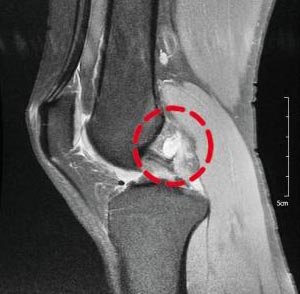

李相花はインタビュー中、かなりの頻度で顔をしかめた。腫瘍がある左膝が痛むという。来シーズンに備えてリハビリを開始し、しばらく休んでいたレゴの組み立てをまた始めたとのことだ。